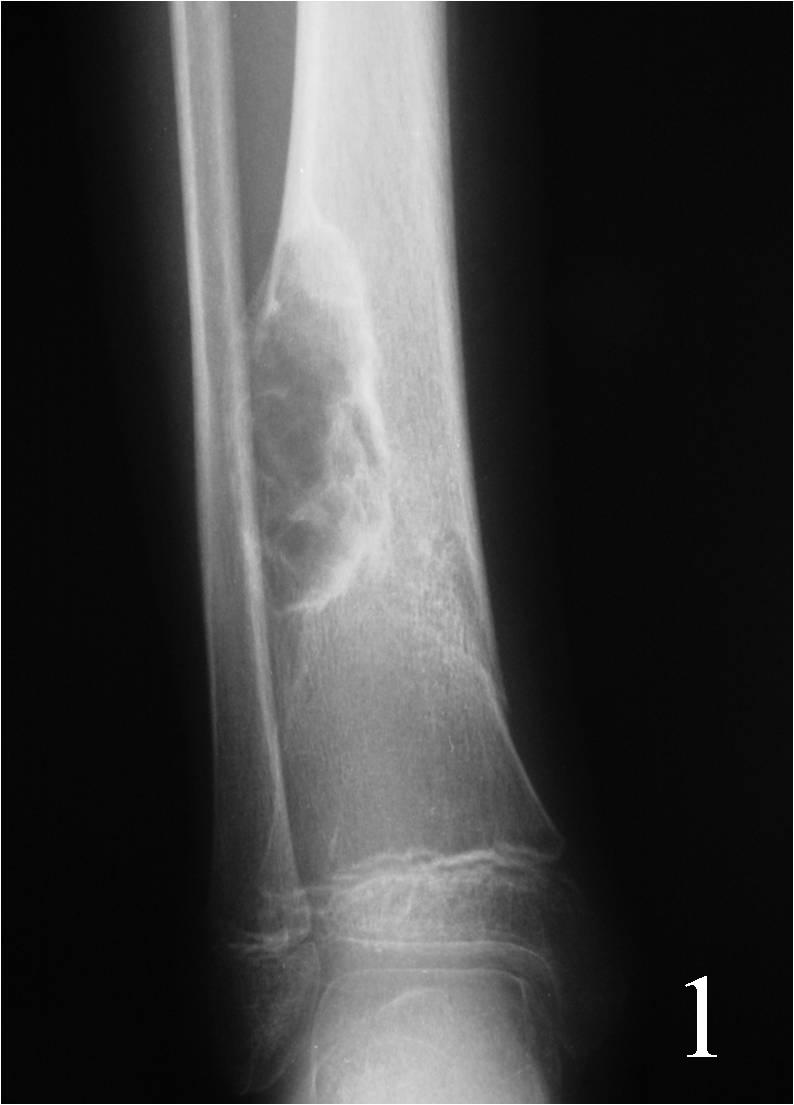

Radiology Non Ossifying Fibroma . Fibroxanthomas can be divided into: Nonossifying fibromas (nofs) are the most common benign (not cancerous) bone tumor in children. It is estimated that 30 to 40% of people under the age of 20 have an nof, although few will. Nof is a do not touch lesion. It is considered a type of fibrous xanthoma of bone and is identical to fibrous cortical defect (fcd), which occurs in younger children. Fibrous cortical defect (fcd) is a fibroxantoma smaller than 2 cm. Nonossifying fibroma is a common benign finding encountered in the practice of radiology. The lesions are usually asymptomatic and found incidentally on imaging studies. Usually a “don't touch” lesion. However, prophylactic curettage and bone grafting.

Fibroxanthomas can be divided into: Nonossifying fibromas (nofs) are the most common benign (not cancerous) bone tumor in children. Usually a “don't touch” lesion. Nof is a do not touch lesion. Fibrous cortical defect (fcd) is a fibroxantoma smaller than 2 cm. The lesions are usually asymptomatic and found incidentally on imaging studies. Nonossifying fibroma is a common benign finding encountered in the practice of radiology. However, prophylactic curettage and bone grafting. It is estimated that 30 to 40% of people under the age of 20 have an nof, although few will. It is considered a type of fibrous xanthoma of bone and is identical to fibrous cortical defect (fcd), which occurs in younger children.

Radiology Non Ossifying Fibroma It is considered a type of fibrous xanthoma of bone and is identical to fibrous cortical defect (fcd), which occurs in younger children. Usually a “don't touch” lesion. Fibrous cortical defect (fcd) is a fibroxantoma smaller than 2 cm. Nof is a do not touch lesion. Nonossifying fibroma is a common benign finding encountered in the practice of radiology. It is considered a type of fibrous xanthoma of bone and is identical to fibrous cortical defect (fcd), which occurs in younger children. Fibroxanthomas can be divided into: Nonossifying fibromas (nofs) are the most common benign (not cancerous) bone tumor in children. It is estimated that 30 to 40% of people under the age of 20 have an nof, although few will. However, prophylactic curettage and bone grafting. The lesions are usually asymptomatic and found incidentally on imaging studies.